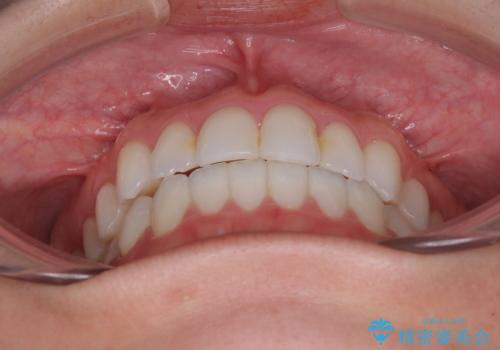

前歯のクロスバイトを治したい インビザラインによる矯正治療

- 前歯のデコボコとクロスバイトを治したいとのことで来院された患者様です。

上下顎ともに歯列全体の側方拡大とIPR(歯と歯の間を削る)によってデコボコとクロスバイトが解消するように設計し、インビザラインにより治療を行うこととしました。

下顎骨の左側への骨格的なずれが強く、上下の正中の位置合わせや奥歯の咬み合わせ構築に苦労しました。